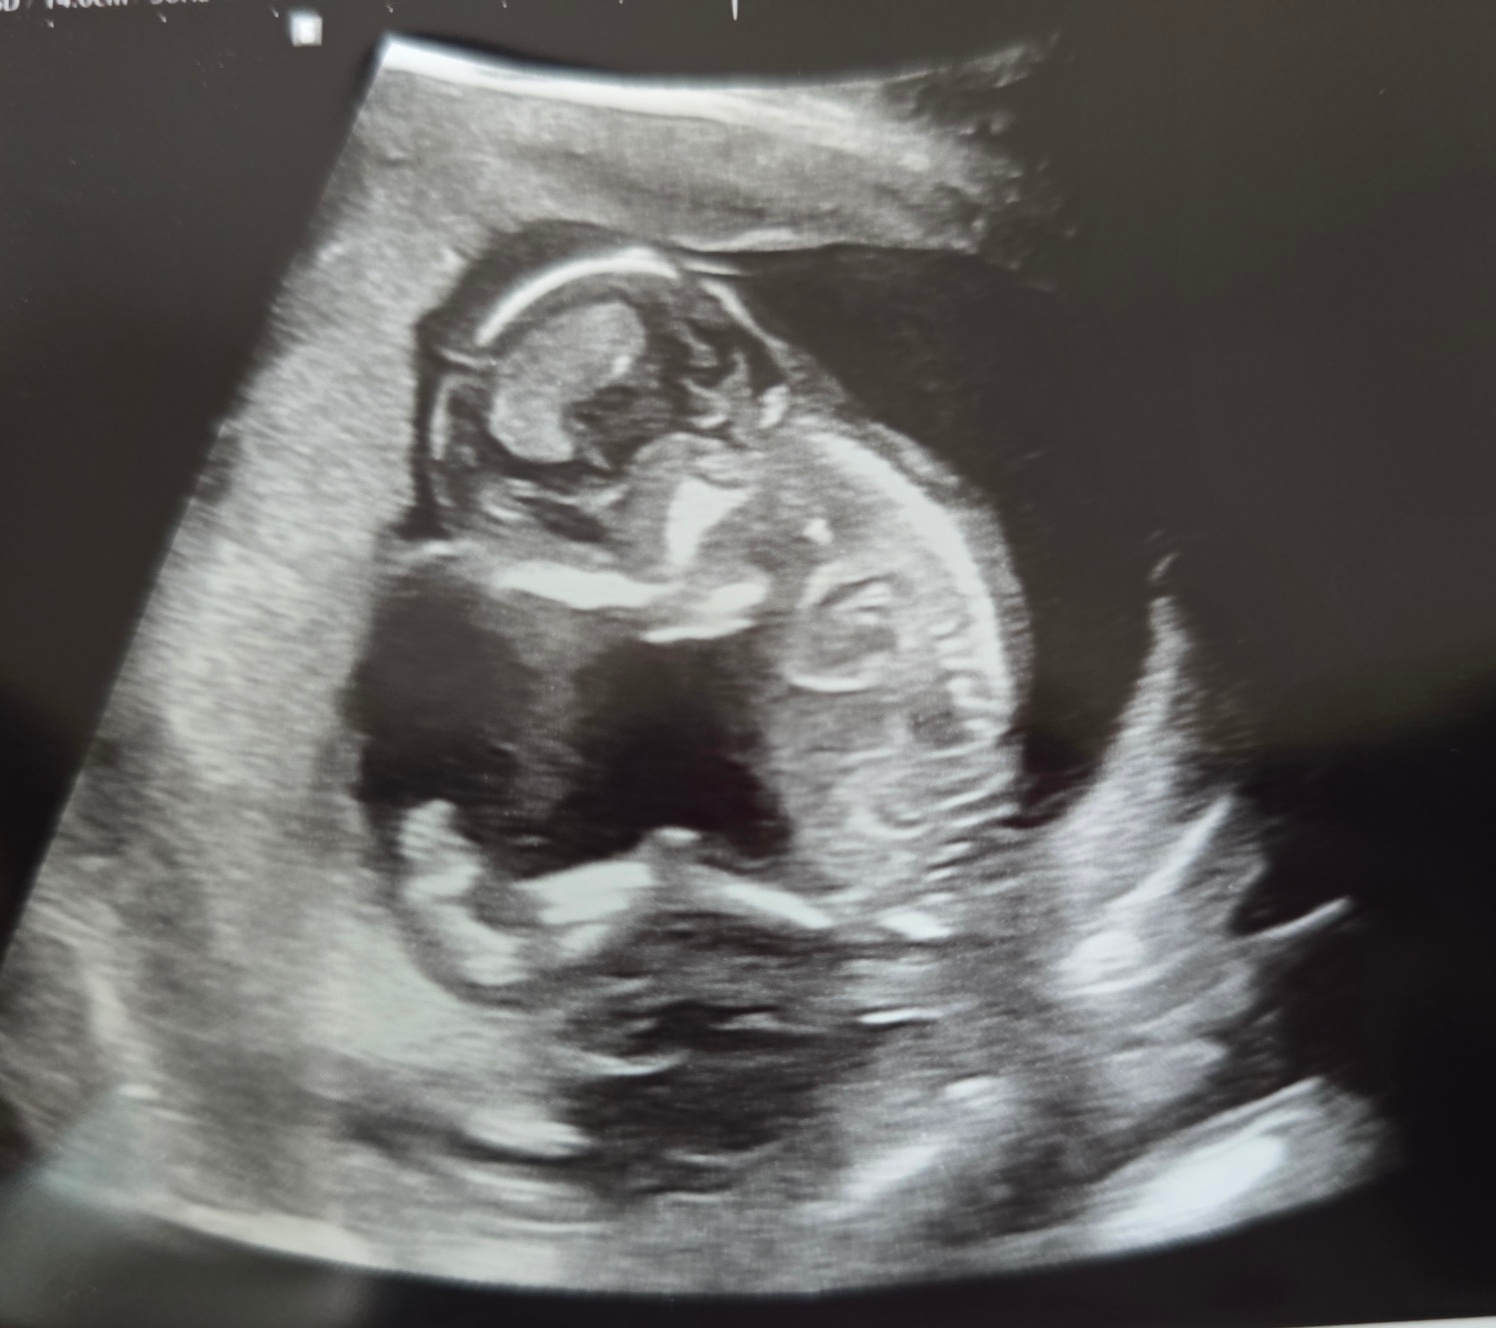

양수검사는 16주 이후부터 가능하다고 들었는데 선생님께서 초음파를 보시곤 오늘도 할 수 있을 것 같다 말씀해 주셔서

당일에 검사를 하고 왔다.

내 품에서 이렇게 심장도 쿵쾅쿵쾅 우렁차게 뛰고 있는 너를 보낼 자신이 없어 뚝딱아.